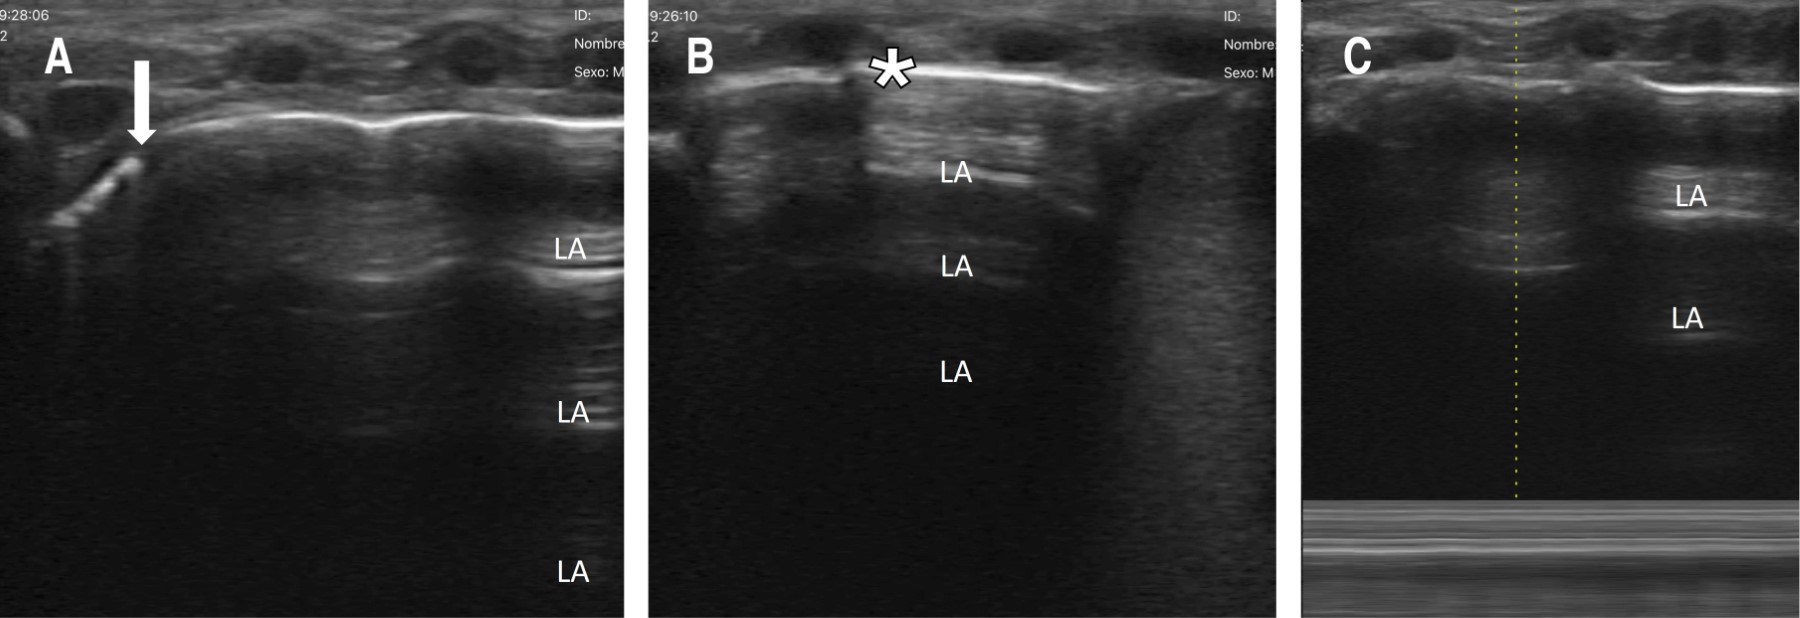

Dado que el neumotórax se consideró que era pequeño, solamente se mantuvo en vigilancia. Al día siguiente, en un nuevo UP ya no se observó, por lo que se determinó que el neumotórax se había resuelto (Figura 3). El paciente se extubó al quinto día y, al concluir ciclo de antibióticos, se egresó a su domicilio sin complicaciones.

Figura 3